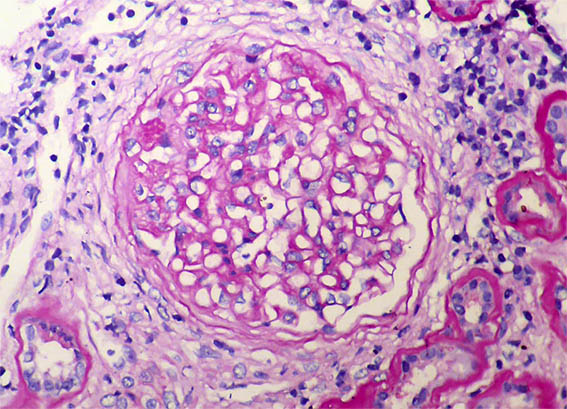

Figure 2. H&E, X400.